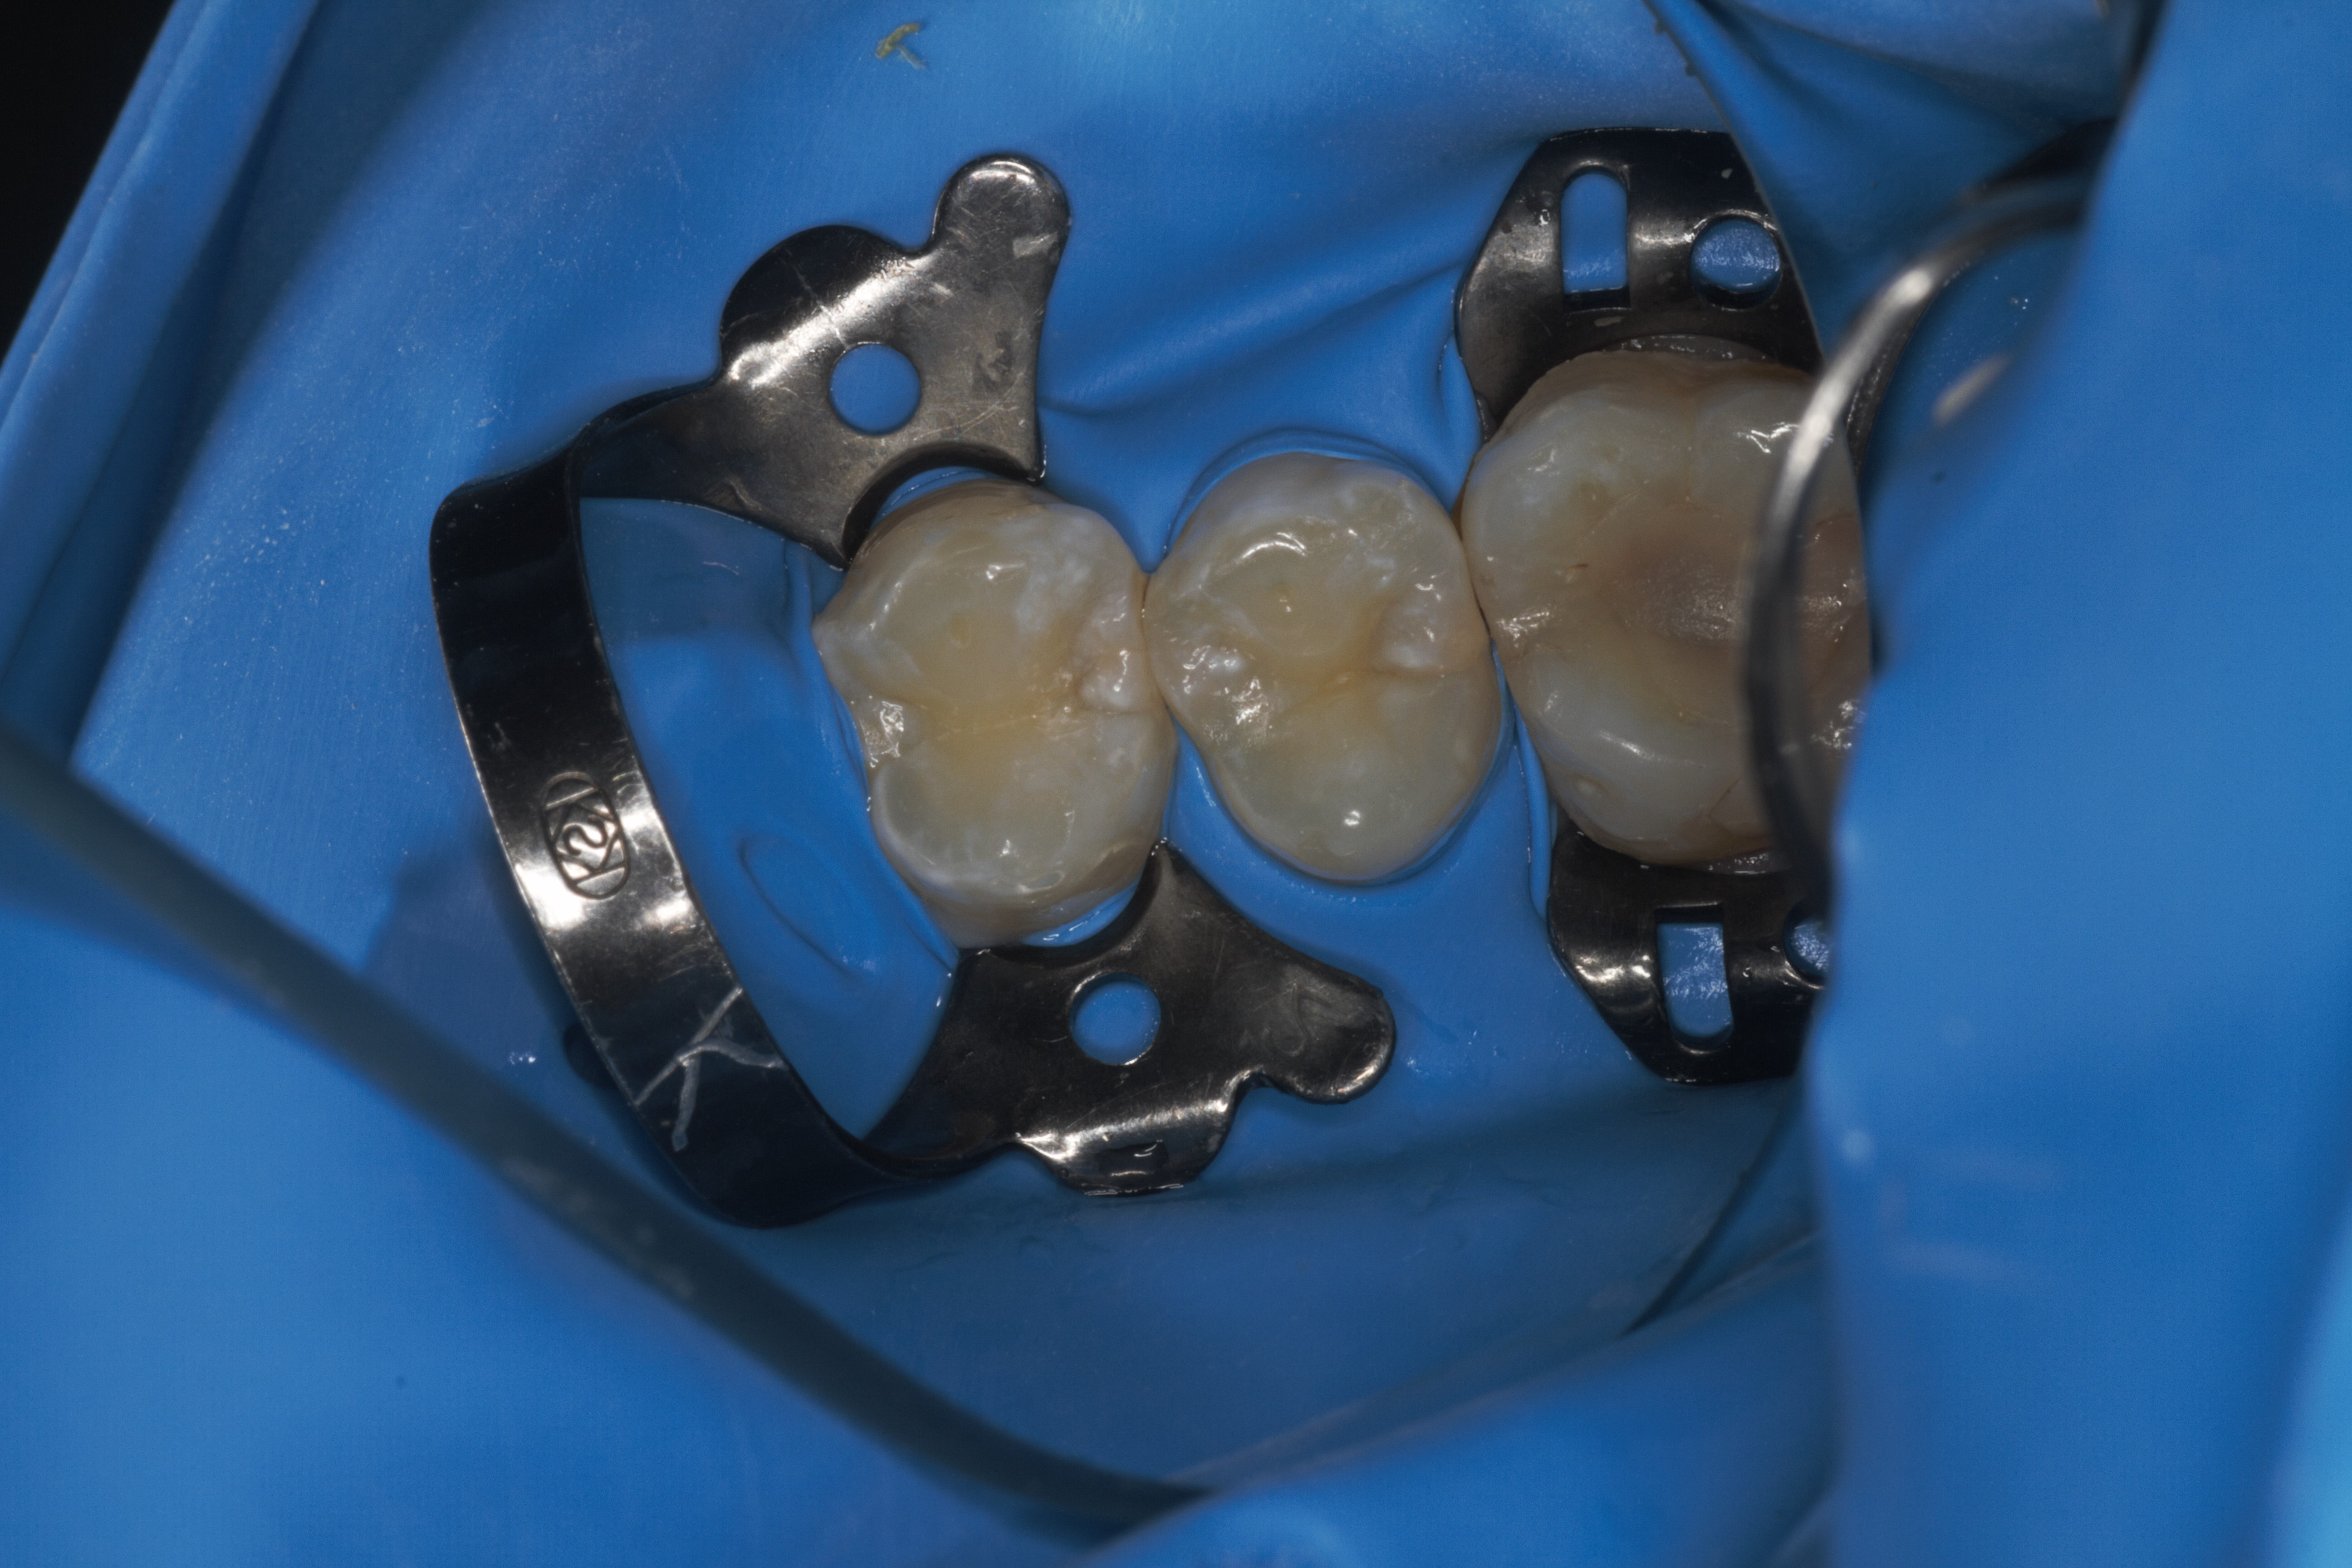

- Эстетическая реставрации жевательной и фронтальной группы зубов современными пломбировочными материалами, диагностика кариеса на ранних этапах развития, предупреждение образования вторичного кариеса в области запломбированных зубов

- 2015г."Учебный курс по непрямым реставрациям зубов", Стомпорт.

- 2015г.Художественная реставрация зубов. Методика Сергея Радлинского.

- 2013г.обучение "Новые подходы в лечении кариеса", "Новые подходы в реставрации зубов", Dentsply